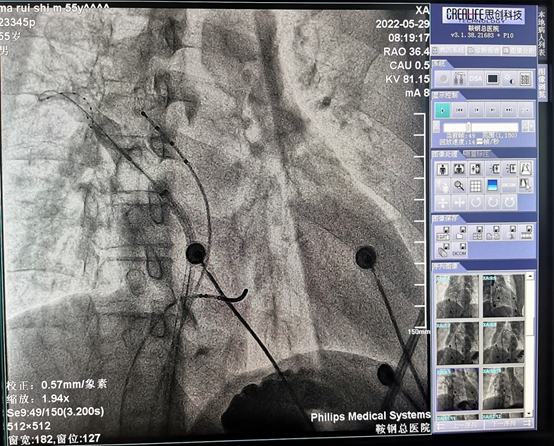

这两例房颤患者均曾就诊于我院房颤门诊,其中一例为阵发性房颤,症状反复发作,药物治疗效果不佳;另一例为持续性房颤,病史小于1年,病人有积极的治疗意愿。两名患者顺利完成房颤冷冻消融手术,术中房颤心律成功转复窦性心律。